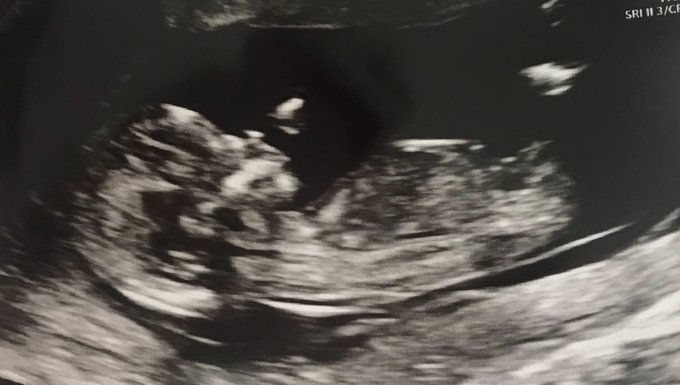

Samantha and I would like to announce Baby Wade due early October. We’re totally in love and excited ❤️ 4 months and counting! @sammimarsh1